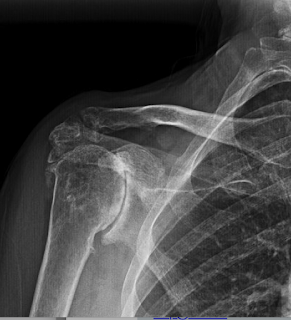

What surgical treatments should be considered for a 72 year old woman with shoulder pain and stiffness and these radiographs? Her active flexion is to 100 degrees.

Of note she used to pitch softball and hardball, but hasn't been able to throw in 25 years. She single-handedly takes care of a 13 acre property.

She wished to avoid the potential risks and limitations of a reverse total shoulder and opted for a cuff tear arthropathy hemiarthroplasty (see this link and this link).